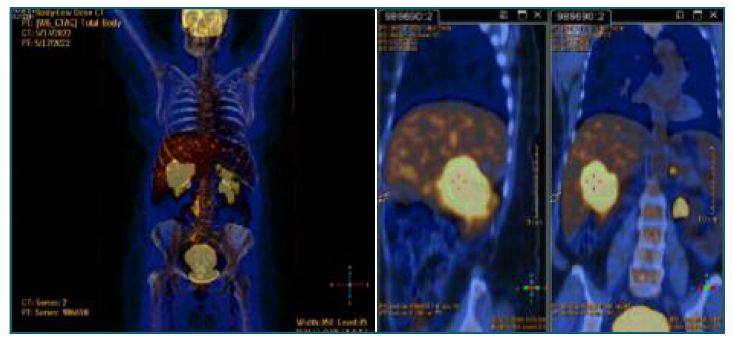

69 years old, obstetric index 3003, menopause at 51 years old, with a history of arterial hypertension. The patient was referred to the endometrial pathology appointment due to abnormal postmenopausal uterine bleeding and endometrial thickening of 7 mm associated with a 15 Kg weight loss in the last few months. The gynecological examination was unremarkable. The hysteroscopy revealed an intracavitary neoformation with suspicious vascularization, which was biopsied; the specimen was sent for anatomopathological study, which revealed a high-grade CD20+ non-Hodgkin B lymphoma, whose morphology and immunohistochemical profile were compatible with diffuse large B cell lymphoma, molecular subtype ABC (Hans algorithm); high ki67 proliferative index (about 80%). The patient was referred to the oncological hematology appointment. Complementary diagnostic tests (thoraco-abdominopelvic CT and PET) detected a lesion in the right kidney with hepatic, left adrenal and uterine infiltration, suggesting lymphoproliferative involvement in these locations - stage IV-B in the Ann Arbor classification (Figure 2). 6 cycles of therapy with rituximab, cyclophosphamide, doxorubicin, vincristine, and prednisolone (R-CHOP) have been completed. The patient has a thoraco-abdominopelvic CT reevaluation scheduled.